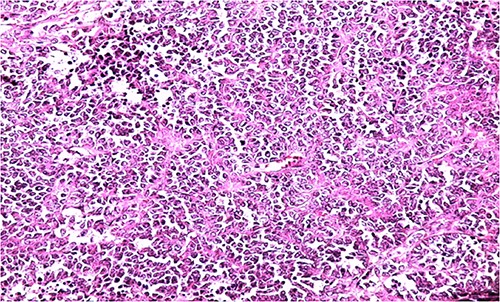

Biologically, the CA 125 tumor marker was at 126.2 IU/ml. The patient underwent a left adnexectomy and an omentectomy (small omentum). Macroscopically, the ovarian mass was smooth on the surface and fleshy on section with the presence of necrotic and hemorrhagic changes. On the histological level, the tumoral proliferation presents a diffuse architecture formed by sheets and clusters separated by fine fibrous septa. Tumor cells are rounded, small, and monomorphic with hyperchromatic, finely nucleolated nuclei and reduced cytoplasm. Mitotic activity is high (36 mitoses/10 HPF) (Figs 3 and 4). The samples taken from the small omentum were tumorous. An immunohistochemical study was carried out and showed diffuse positive expression by tumor cells of Vimentin, and focal by antibodies (Cytokeratin AE1/AE3, EMA, CD99, WT1, Inhibin, and SALL4) and an absence of expression by antibodies (CD45, Chromogranin, PAX8, and AFP) (Figs 5–7).

HE section showing diffuse sheets of small, closely packed round cells with scant cytoplasm separated by fibrous septa (x200).